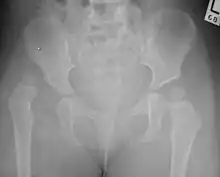

| Congenital dislocation of the left hip in an elderly person. Closed arrow marks the acetabulum, open arrow the femoral head. | |

Hip dysplasia is an abnormality of the hip joint where the socket portion does not fully cover the ball portion, resulting in an increased risk for joint dislocation.[1] Hip dysplasia may occur at birth or develop in early life.[1] Regardless, it does not typically produce symptoms in babies less than a year old.[3] Occasionally one leg may be shorter than the other.[1] The left hip is more often affected than the right.[3] Complications without treatment can include arthritis, limping, and low back pain.[3]